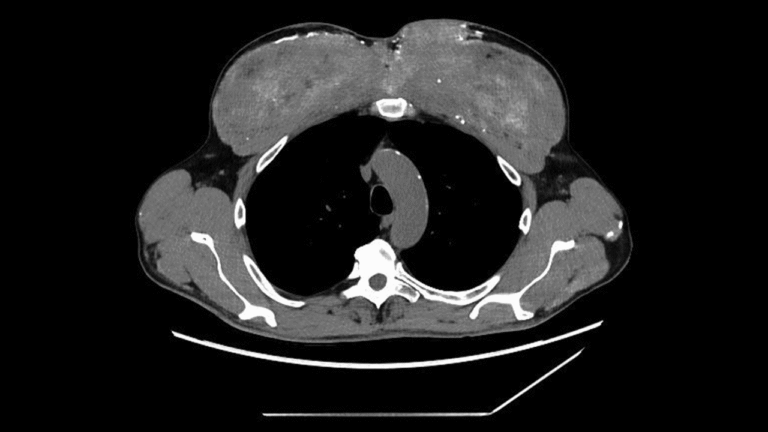

The man was generally stable, but a physical exam showed noticeable changes in his upper-arm and chest muscles, matching the irregularities seen on the scans. The doctors then revisited the patient’s medical history, and he shared a crucial detail: starting about 30 years earlier, he had started receiving “unknown intramuscular injections (probably containing testosterone)” into his chest and upper-arm muscles to enlarge them, according to a report of his case.

Blood tests showed that the man’s calcium-controlling parathyroid hormone was markedly low, ruling out a common hormonal cause of high calcium. The man also had no signs of hidden cancers in his digestive tract, no abnormalities on a urology evaluation, and no signs of an autoimmune condition. With other causes excluded, the medical team biopsied one of the abnormal muscle regions.

The diagnosis: Under the microscope, the muscle was filled with a silicone-like, oil-based substance and surrounded by dense calcium deposits. The team deduced that the man’s past muscular injections probably contained synthol, a substance made primarily of oil that visually “plumps” up muscles, essentially inflating them like water balloons.

In this case, the synthol had triggered a persistent foreign-body reaction — the body essentially responding to material it could not break down. Over time, this reaction produced scarring and calcification, storing large amounts of calcium inside the muscle. And eventually, that calcium made its way into his bloodstream.